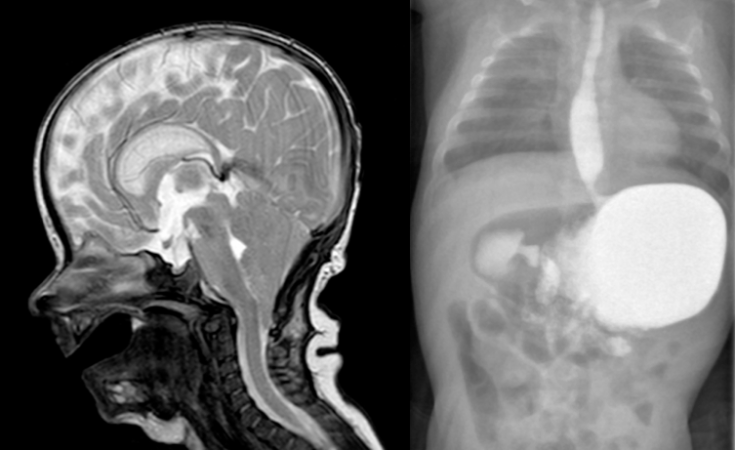

il existe fréquemment un engagement tonsillaire (Chiari) se constituant rapidement ou présent d’emblée.

- l’IRM montre la compression cérébrale, la compression des sinus veineux et la circulation de suppléance par les veines trans-osseuses, l’engagement tonsillaire

engagement tonsillaire constitué en quelques mois après la naissance